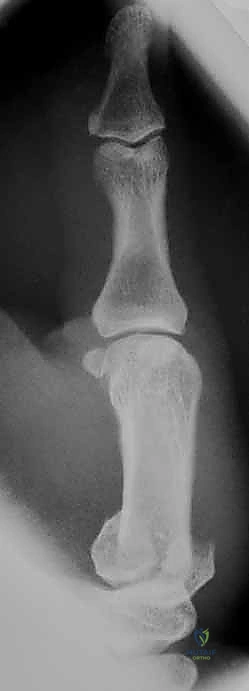

2. التصوير بالأشعة السينية (X-rays)

هي الأداة التشخيصية الأولى والأهم. يتم إجراء صور أشعة بزوايا محددة جداً:

* المنظور الأمامي الخلفي (AP View).

* المنظور الجانبي الحقيقي (True Lateral View): وهو ضروري جداً لتقييم مدى الخلع أو الانزياح في المفصل.

* منظور روبرت (Robert's View): وضعية خاصة للأشعة السينية تظهر مفصل الإبهام الرسغي السنعي بوضوح تام وتكشف عن أدق التفاصيل في كسور بينيت ورولاندو.